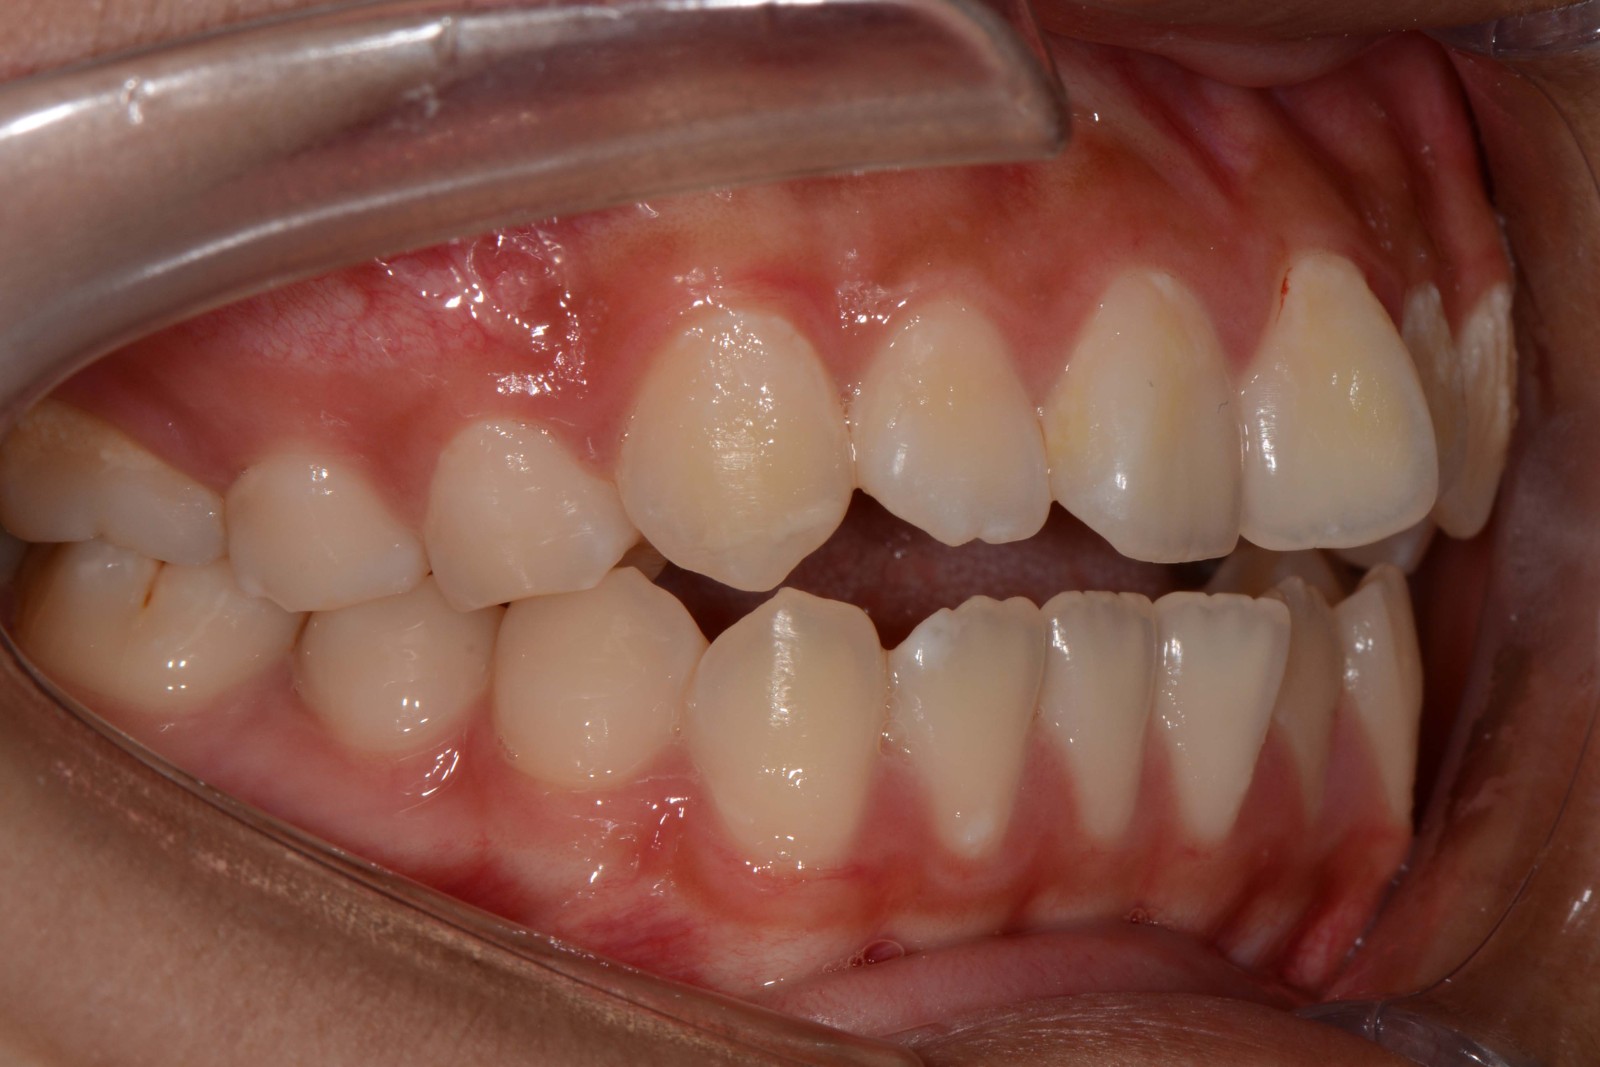

患者:14岁女性

主诉:前牙咬不住,进食不便

前牙区开颌3mm

诊断:安氏II类错颌畸形  开颌

矫治前: